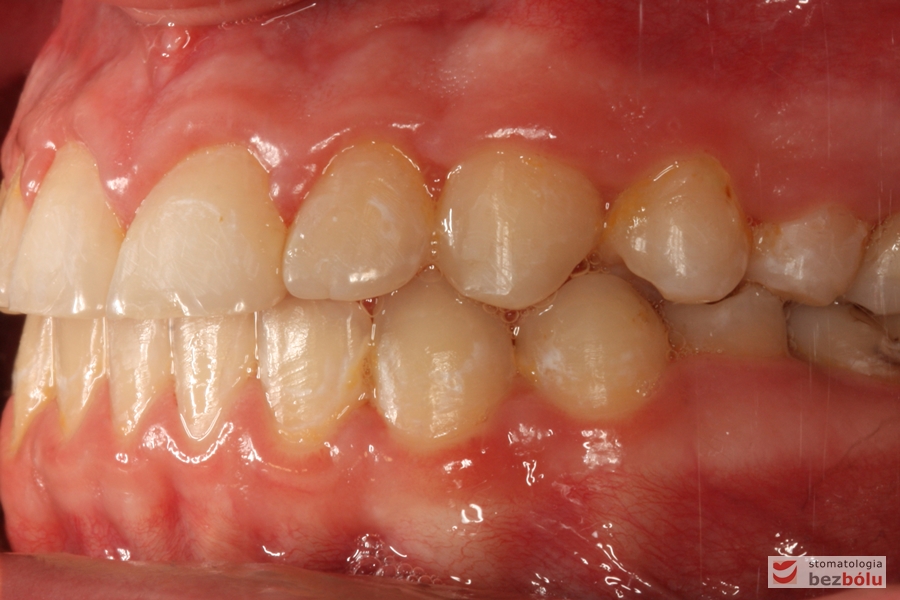

Rodzice zgłosili się z pacjentem celem rutynowej kontroli ortodontycznej. Wykonano OPG i po analizie modeli diagnostycznych stwierdzono brak miejsca dla wyrzynania dolnej prawej piątki stałej oraz zwężenie szczęki wraz z rotacją górnych zębów szóstych. W łuku górnym w pierwszym etapie leczenia zastosowano Rotator, celem odrotowania 6-tek stałych oraz ekspansji łuku w wymiarze poprzecznym. Następnie zamontowano aparat stały metalowy do uszeregowania zębów w łuku. W łuku dolnym miejsce odtwarzano stosując aparat stały i odpowiednią mechanikę leczenia. Leczenie aktywne trwało 3,5 roku, po czym zastosowano terapię retencyjną (retainer stały w żuchwie oraz Płytkę Hawley’a w szczęce).